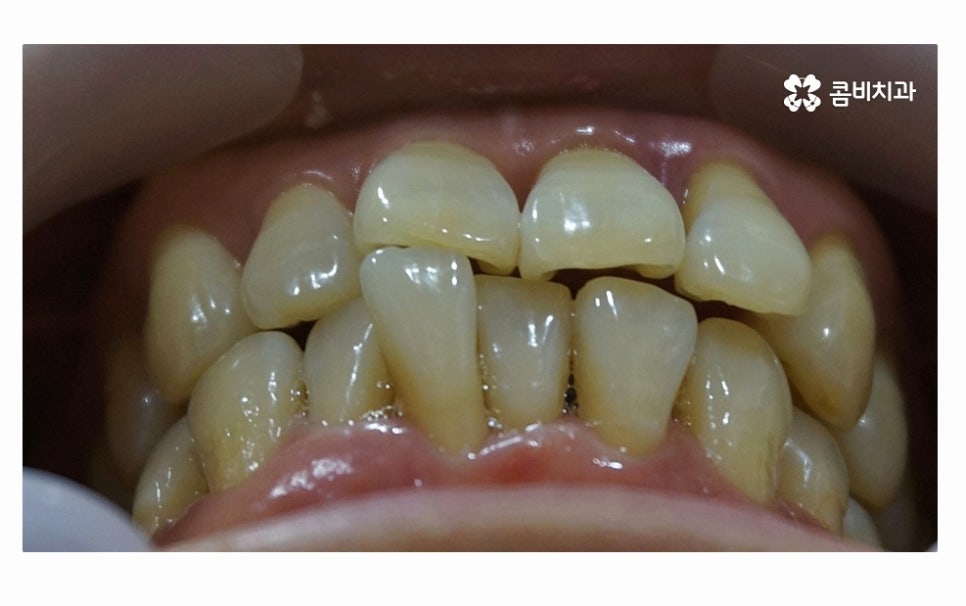

오늘 소개드릴 환자분의 케이스는 치아 상실의 요인이

잇몸질환이 심해져서 치아 뿌리까지 염증이 발생되었고

결국 어금니 발치 까지 이어진 사례라고 할 수 있는데요.

사진에서 보시는 것처럼 치아 사이에 빈 공간도 많고

잇몸이 내려앉아서 치아의 하단부도 많이 드러난 상태인데

어금니 발치까지 이어지도록 청결 관리에 악영향을 준 요소로는

평소의 식습관이나 칫솔질 부분도 컸겠지만

불규칙한 치열과 옆으로 누운 사랑니도 영향이 컸으며